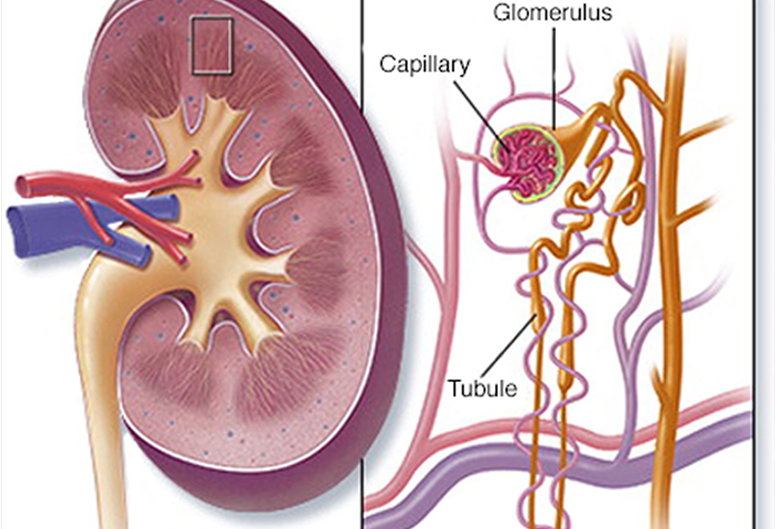

Fellowship in Glomerular Diseases (GlomCon) by the Glomerular Disease Study and Trial

Consortium.